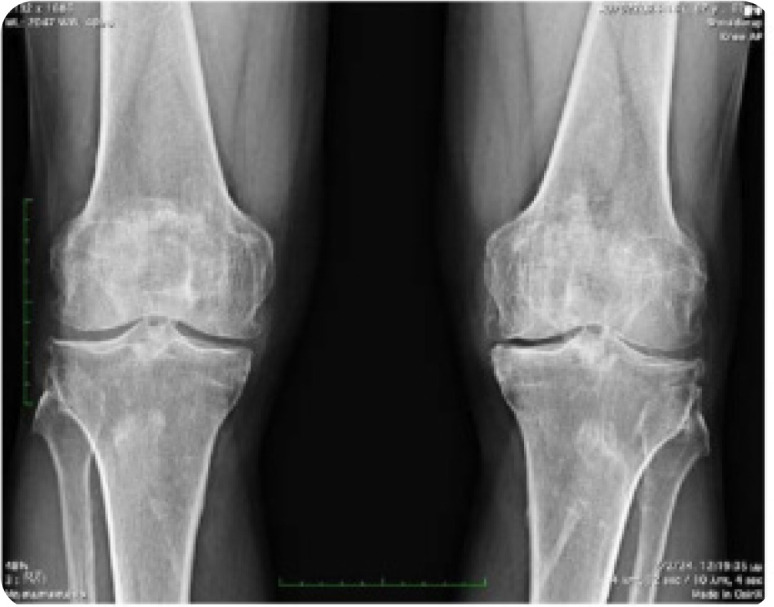

Diffuse Idiopathic Skeletal Hyperostosis, beyond the Axial Skeleton: Extra-spinal DISH.